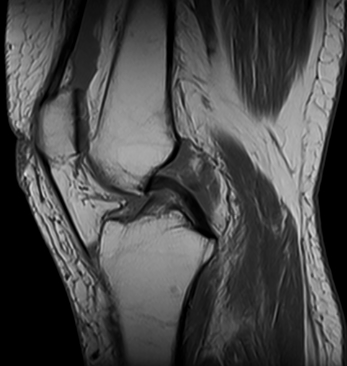

La Resonancia magnética (RMN) es un método de imagen multiplanar no invasivo, basado en la interacción entre la radiofrecuencia, los campos magnéticos y ciertos núcleos en el cuerpo humano (generalmente núcleos de hidrógeno del agua), después que el cuerpo ha sido introducido en un campo magnético fuerte. La información obtenida es procesada por un ordenador y transformada en imágenes del cuerpo humano.

La RM consigue información sobre la estructura del cuerpo permitiendo diferenciar entre tejidos normales y anormales lo que la convierte en una técnica muy sensible para detectar enfermedad. Esta sensibilidad está basada en un alto grado de contraste debido a las variaciones en las propiedades de relajación magnética de los diferentes tejidos, tanto normales como anormales.